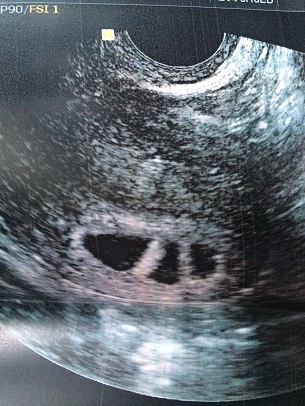

After a year of irregular cycles and no success, I finally decided to visit a specialist. It turned out I had a mild case of endometriosis and PCOS. A laparoscopic surgery and one cycle of hormonal injections later, in the span of 6 months, I had my first positive pregnancy test. I was so excited I booked my first appointment with a renowned OBGYN in Brazil when it came to natural births. Everything was going according to plan until I actually had my first ultrasound and saw three gestational sacks. I was having triplets.